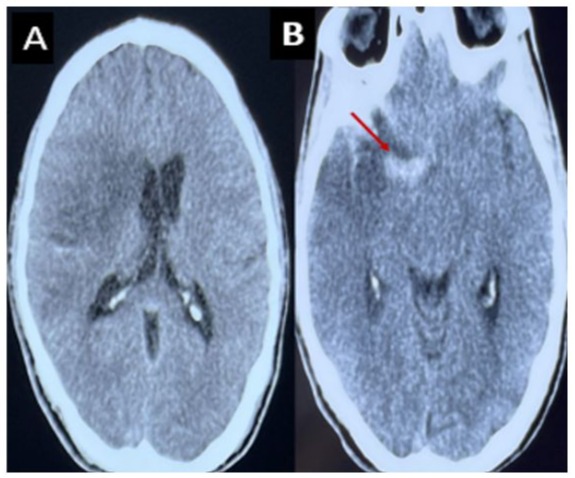

H.E a 26-year-old man with a history of active smoking, cannabis use, and chronic alcohol consumption. He had no history of recurrent tonsillitis, childhood heart disease, autoimmune disorders, known hereditary diseases, cervical trauma, or heavy lifting. He was admitted to the neurological emergency unit 3 days after sudden onset of proportional left hemiplegia, dysarthria, and Claude Bernard-Horner syndrome. An urgent brain CT scan revealed an ischemic stroke in the middle cerebral artery territory with a hyperdense sylvian artery sign (Figure 1). Brain MRI showed an intracranial dissection of the right carotid and sylvian arteries (Figure 2). One week later, digital subtraction angiography revealed a pseudoaneurysmal dilation at the origin of the right sylvian artery, resulting from the progression of the intracranial dissection (Figure 3). The patient was placed on antiplatelet therapy. The etiological assessment of his ischemic stroke revealed mitro-aortic infective endocarditis complicated by an abscess of the membranous septum, severe aortic regurgitation, and moderate mitral regurgitation. Notably, his initial Transthoracic Echocardiography (TTE) six days prior revealed infected endocarditis without concomitant valvulopathy. Blood cultures were negative. Biological analyses showed absence of inflammatory syndrome with negative Procalcitonin, positive TPHA and VDRL serology in the blood, while Cerebrospinal Fluid (CSF) analysis revealed a clear, normotensive fluid with normal biochemical and bacteriological findings and negative TPHA and VDRL serology in the Cerebrospinal Fluid (CSF), the other serologies (serology of hepatitis B and C, HIV) were negative. The patient received intravenous antibiotic therapy with ceftriaxone (2g/day) for six weeks and gentamicin (160mg/day) for two weeks, with an indication for valve replacement surgery. Neurological deficits partially regressed (NIHSS at first day=9, at one month=5, and at three months=2, with a modified Rankin Scale score of 3 at three months).

Figure 1: CT scan without contrast, axial section showing a right deep and superficial sylvian ischemic stroke with mass effect on the homolateral ventricles (A). Spontaneously hyperdense appearance of the right Sylvian artery (B).